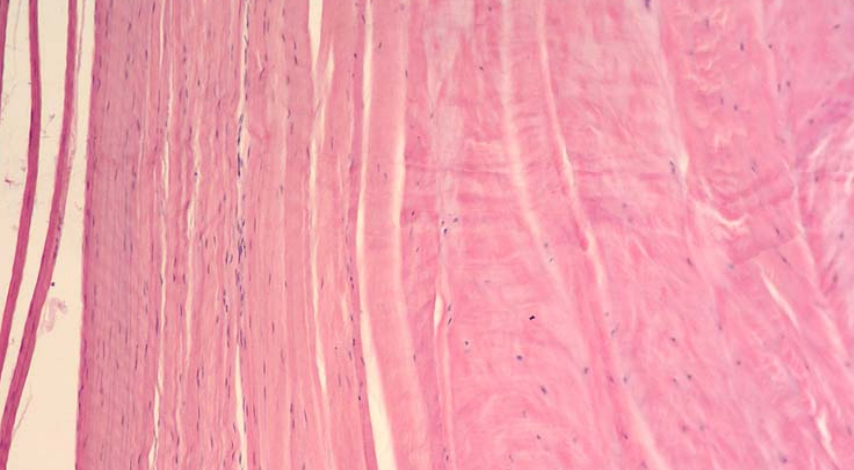

what connective tissue present?

what muscle is present?

tendon: dense regular CT

skeletal muscle

multinucleated, cross striations

endomysein: reticular fibers

perimyseins: loose CT